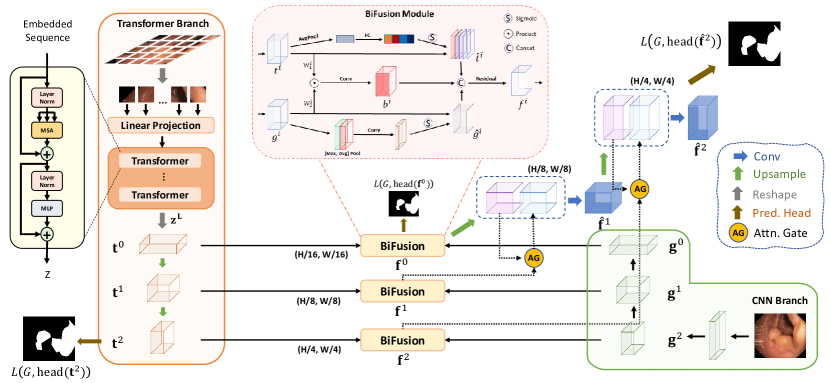

As shown in Fig. 1, TransFuse consists of two parallel branches processing information differently: 1) CNN branch, which gradually increases the receptive field and encodes features from local to global; 2) Transformer branch, where it starts with global self-attention and recovers the local details at the end. Features with same resolution extracted from both branches are fed into our proposed BiFusion Module, where self-attention and bilinear Hadamard product are applied to selectively fuse the information. Then, the multi-level fused feature maps are combined to generate the segmentation using gated skip-connection [20].

Transformer Branch. The design of Transformer branch follows the typical encoder-decoder architecture. Specifically, the input image is first evenly divided into patches, where is typically set to 16. The patches are then flattened and passed into a linear embedding layer with output dimension , obtaining the raw embedding sequence . To utilize the spatial prior, a learnable positional embeddings of the same demension is added to . The resulting embeddings is the input to Transformer encoder, which contains layers of multiheaded self-attention (MSA) and Multi-layer Perceptron (MLP). We highlight that the self-attention (SA) mechanism, which is the core principal of Transformer, updates the states of each embedded patch by aggregating information globally in every layer:

where , is the projection matrix and vector are the row of and , respectively. MSA is an extension of SA that concatenates multiple SAs and projects the latent dimension back to , and MLP is a stack of dense layers (refer to [7] for details of MSA and MLP). Layer normalization is applied to the output of the last transformer layer to obtain the encoded sequence . For the decoder part, we use progressive upsampling (PUP) method, as in SETR [32]. Specifically, we first reshape back to , which could be viewed as a 2D feature map with channels. We then use two consecutive standard upsampling-convolution layers to recover the spatial resolution, where we obtain and , respectively. The feature maps of different scales , and are saved for late fusion with corresponding feature maps of the CNN branch.

CNN Branch. Traditionally, features are progressively downsampled to and hundreds of layers are employed in deep CNNs to obtain global context of features, which results in very deep models draining out resources. Considering the benefits brought by Transformers, we remove the last block from the original CNNs pipeline and take advantage of the Transformer branch to obtain global context information instead. This gives us not only a shallower model but also retaining richer local information. For example, ResNet-based models typically have five blocks, each of which downsamples the feature maps by a factor of two. We take the outputs from the 4th (), 3rd () and 2nd () blocks to fuse with the results from Transformer (Fig. 1). Moreover, our CNN branch is flexible that any off-the-shelf convolutional network can be applied.

BiFusion Module. To effectively combine the encoded features from CNNs and Transformers, we propose a new BiFusion module (refer to Fig. 1) that incorporates both self-attention and multi-modal fusion mechanisms. Specifically, we obtain the fused feature representation by the following operations:

where , , is the Hadamard product and Conv is a 3x3 convolution layer. The channel attention is implemented as SE-Block proposed in [10] to promote global information from the Transformer branch. The spatial attention is adopted from CBAM [30] block as spatial filters to enhance local details and suppress irrelevant regions, as low-level CNN features could be noisy. The Hadamard product then models the fine-grained interaction between features from the two branches. Finally, the interaction features and attended features are concatenated and passed through a Residual block. The resulting feature effectively captures both the global and local context for the current spatial resolution. To generate final segmentation, s are combined using the attention-gated (AG) skip-connection [20], where we have and , as in Fig. 1.

Loss Function. The full network is trained end-to-end with the weighted IoU loss and binary cross entropy loss , where boundary pixels receive larger weights [17]. Segmentation prediction is generated by a simple head, which directly resizes the input feature maps to the original resolution and applies convolution layers to generate maps, where is the number of classes. Following [8], We use deep supervision to improve the gradient flow by additionally supervising the transformer branch and the first fusion branch. The final training loss is given by , where , , are tunnable hyperparameters and is groundtruth.